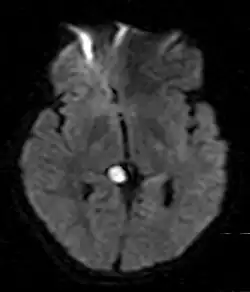

Gehirn

Im Gehirn tritt die Epidermoidzyste als gelappte, unregelmäßige, blumenkohlartige Raumforderung auf. Ihre Dichte ähnelt liquorähnlicher Flüssigkeit, welche keine Kontrastmittelanreicherung aufweist. In der Magnetresonanztomographie ist sie vor allem dadurch zu unterscheiden, dass sie in der Flair-Sequenz nicht vollständig signalsupprimiert ist, d. h., es besteht eine Hyperintensität im Vergleich zu Liquor. In 10 bis 25 % der Fälle sind Verkalkungen vorhanden. Am häufigsten finden sich Epidermoidzysten im Kleinhirnbrückenwinkel (75 %) und im 4. Hirnventrikel (20 %). Sie entstehen beim Embryo aus Einschlüssen an der Oberfläche der Haut während des Neuralrohrverschlusses.